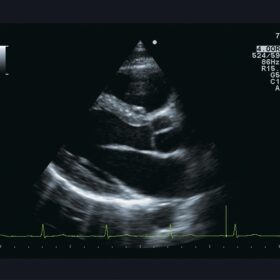

Ultrasound Aloka Prosound Alpha 10 – Image Gallery and Videos

Enhanced image quality ensures more accurate and efficient diagnosis while increasing patient satisfaction. The ideal choice for a large office or hospital imaging department. The Alpha 10 combines a 12 Bit A/D digital beam converter. High powered image processing channels and the exclusive probe technology to take examinations to the next level.

Sophisticated beam control provides high resolution and penetration while minimizing image degradation. While user-oriented operability and ergonomics create the ideal environment for fast and accurate imaging and diagnoses. The Alpha 10’s Extended Pure Harmonic Detection is a digital pure beam-imaging platform. That incorporates state-of-the-art acoustic technology that dramatically improves the clarity of the ultrasound beam formation and signal processing.